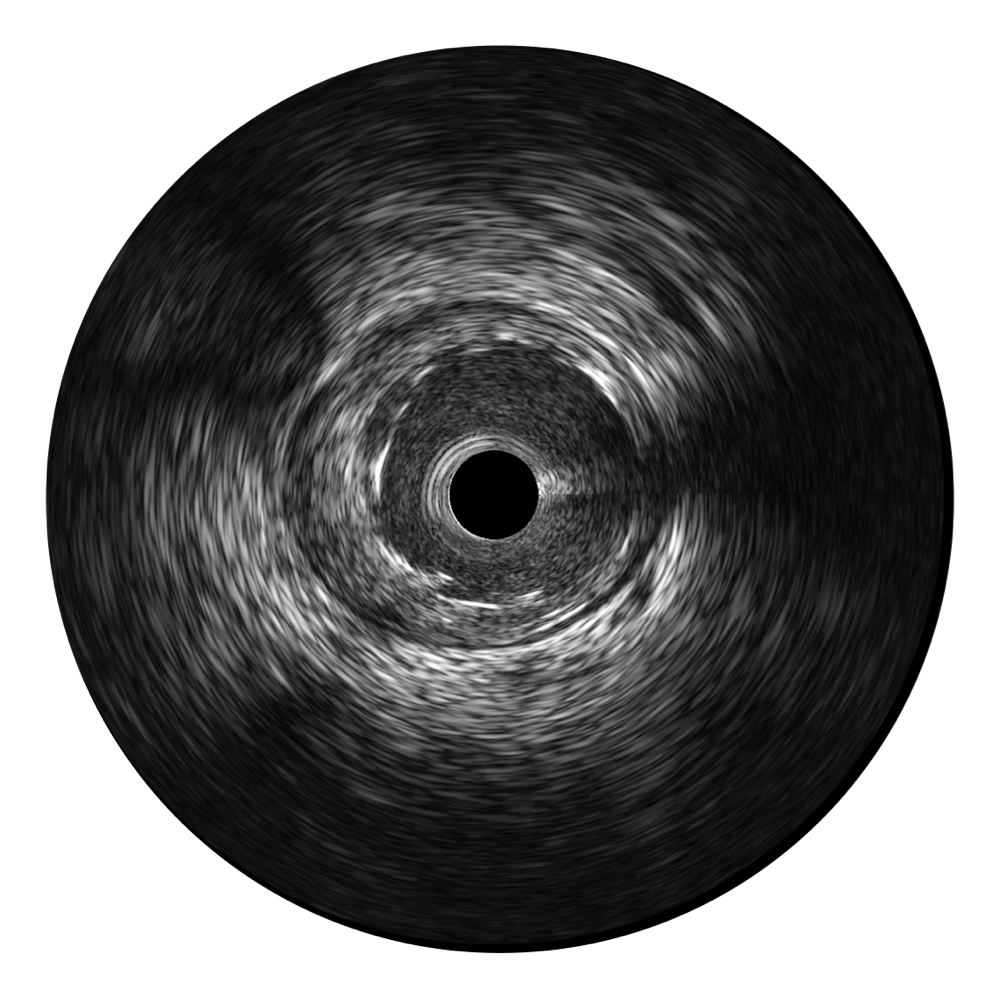

传统IVUS图像

对比传统IVUS导管成像,球速体育入口宽频IVUS图像的近场支架梁显影更细腻,远场中膜外血管仍清晰可辨,兼顾远中近,兼顾分辨力与穿透深度